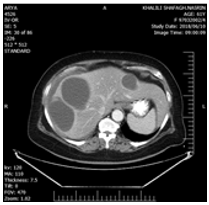

In treatment history, a shoulder Pain was present which not associated with any trauma or GI tract problem. That time she was conscious, only complaining of severe shoulder pain and mild abdominal pain. The shoulder movement was normal. The only physical finding was mild tenderness and guarding in all quadrants of the abdomen. Her blood pressure120/80 mmHg, heart rate was 95 beats min, respiratory rate 18 bpm, WBC=21000. Three days after admission, she had a CXR showed that shoulder joint was normal but in chest mild pleural effusion and atelectasis was present with on the right side. The patient underwent ultrasonography which showed one intact cystic lesion (42x38mm) in the left lobe and two cysts in the right lobe (87x83mm) and (67x4 mm) and computed tomography of abdomen showed as U&S but showed fluid at sub diaphragmatic location and around with on liver (Figures 1-3).

Figure 2: CT-scan of patient show two cystic lesions in the right lobe, which one is partially ruptured and one left lobes with mild effusion in around the liver.